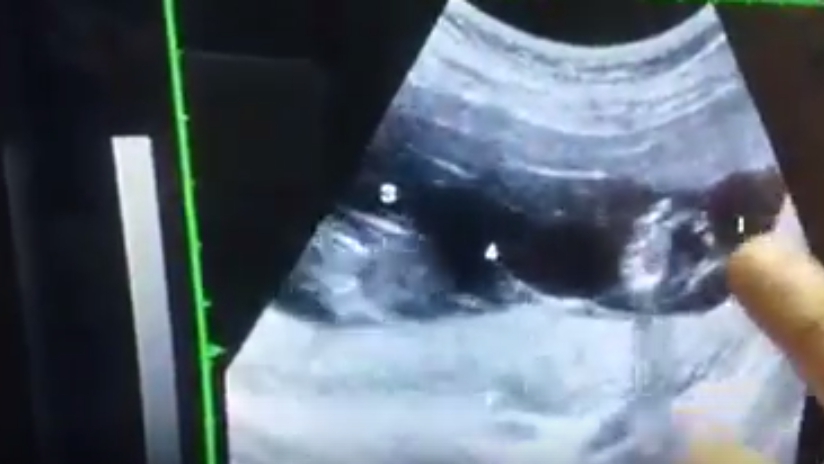

50歲在博元婦產科做試管嬰兒一次四胞胎減成雙胞胎

50歲懐四胞胎

https://www.youtube.com/watch?v=r_ma0T20p4s